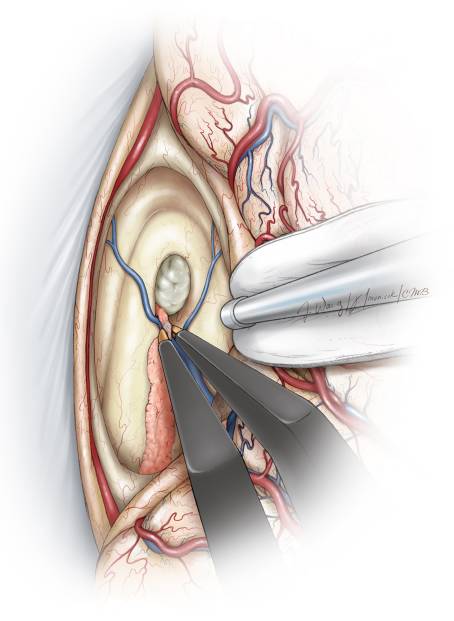

图9. 神经导航是引导术者通过合理而有限的切开胼胝体(左图),从预期的手术角度到达到室间孔的关键所在。2cm的胼胝体切开恰好位于中线右侧,显露右侧脑室(右图)。在脑室汇聚点释放脑脊液进一步松弛额叶。注意用缝线牵引大脑镰上方适当推移上矢状窦。

图10. 将覆盖在Monro孔和静脉角表面的脉络丛前方切断,然后轻柔的钝性分离和电凝。肿瘤通常会扩大室间孔,但是无法提供足以完整切除肿瘤的手术通道(Redrawn from Tew,van Loveren, Keller*)。